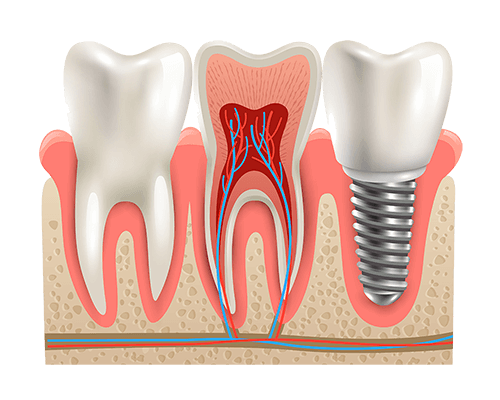

Impossible malheureusement de coller un élément prothétique là-dessus

C’est là qu’interviennent les implants dentaires !

Un implant c’est en fait une racine artificielle qui est mise dans l’os pour pouvoir supporter une nouvelle couronne.

Les implants dentaires représentent donc l’une des avancées majeures en médecine dentaire de ces 40 dernières années. C’est une option durable et efficace sur le long terme pour remplacer une dent perdue.

L’implant se fond dans votre denture et vous offre un sourire sans défaut. Par conséquent, la pose d’implants dentaires connaît un taux de succès qui s’avère très élevé.

La plupart du temps on ne pose pas l’implant en même temps que la couronne. L’implant est d’abord mis en place et on attendra deux mois avant de pouvoir poser la couronne dessus. Pendant ces deux mois il se passe ce qu’on appelle l’ostéointégration.

il faut que l’os soit solidement cicatriser autour de l’implant pour que le traitement puisse durer dans le temps.

Ostéointégration : cicatrisation de l’os autour de l’implant

- Lorsque la racine artificielle ( l’implant) est bien soudée à l’os (ostéointégré), le chirurgien-dentiste installe le pilier en titane. Cet élément relie l’implant à la prothèse.

- Pose de la couronne dentaire sur le pilier (les deux sont fabriqués sur mesure)